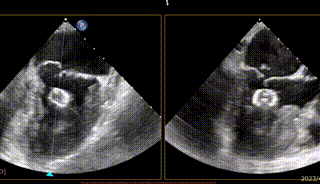

【二尖瓣相关参数】二尖瓣重度反流(继发性:Carpentier II型);A3:21mm P3:13mm,MVOA:5.3cm²,P3脱垂连枷,3区病变,瓣叶质地欠佳。

跨瓣球,跨瓣,方位练习,进鞘

在MultiVue下定位与夹合